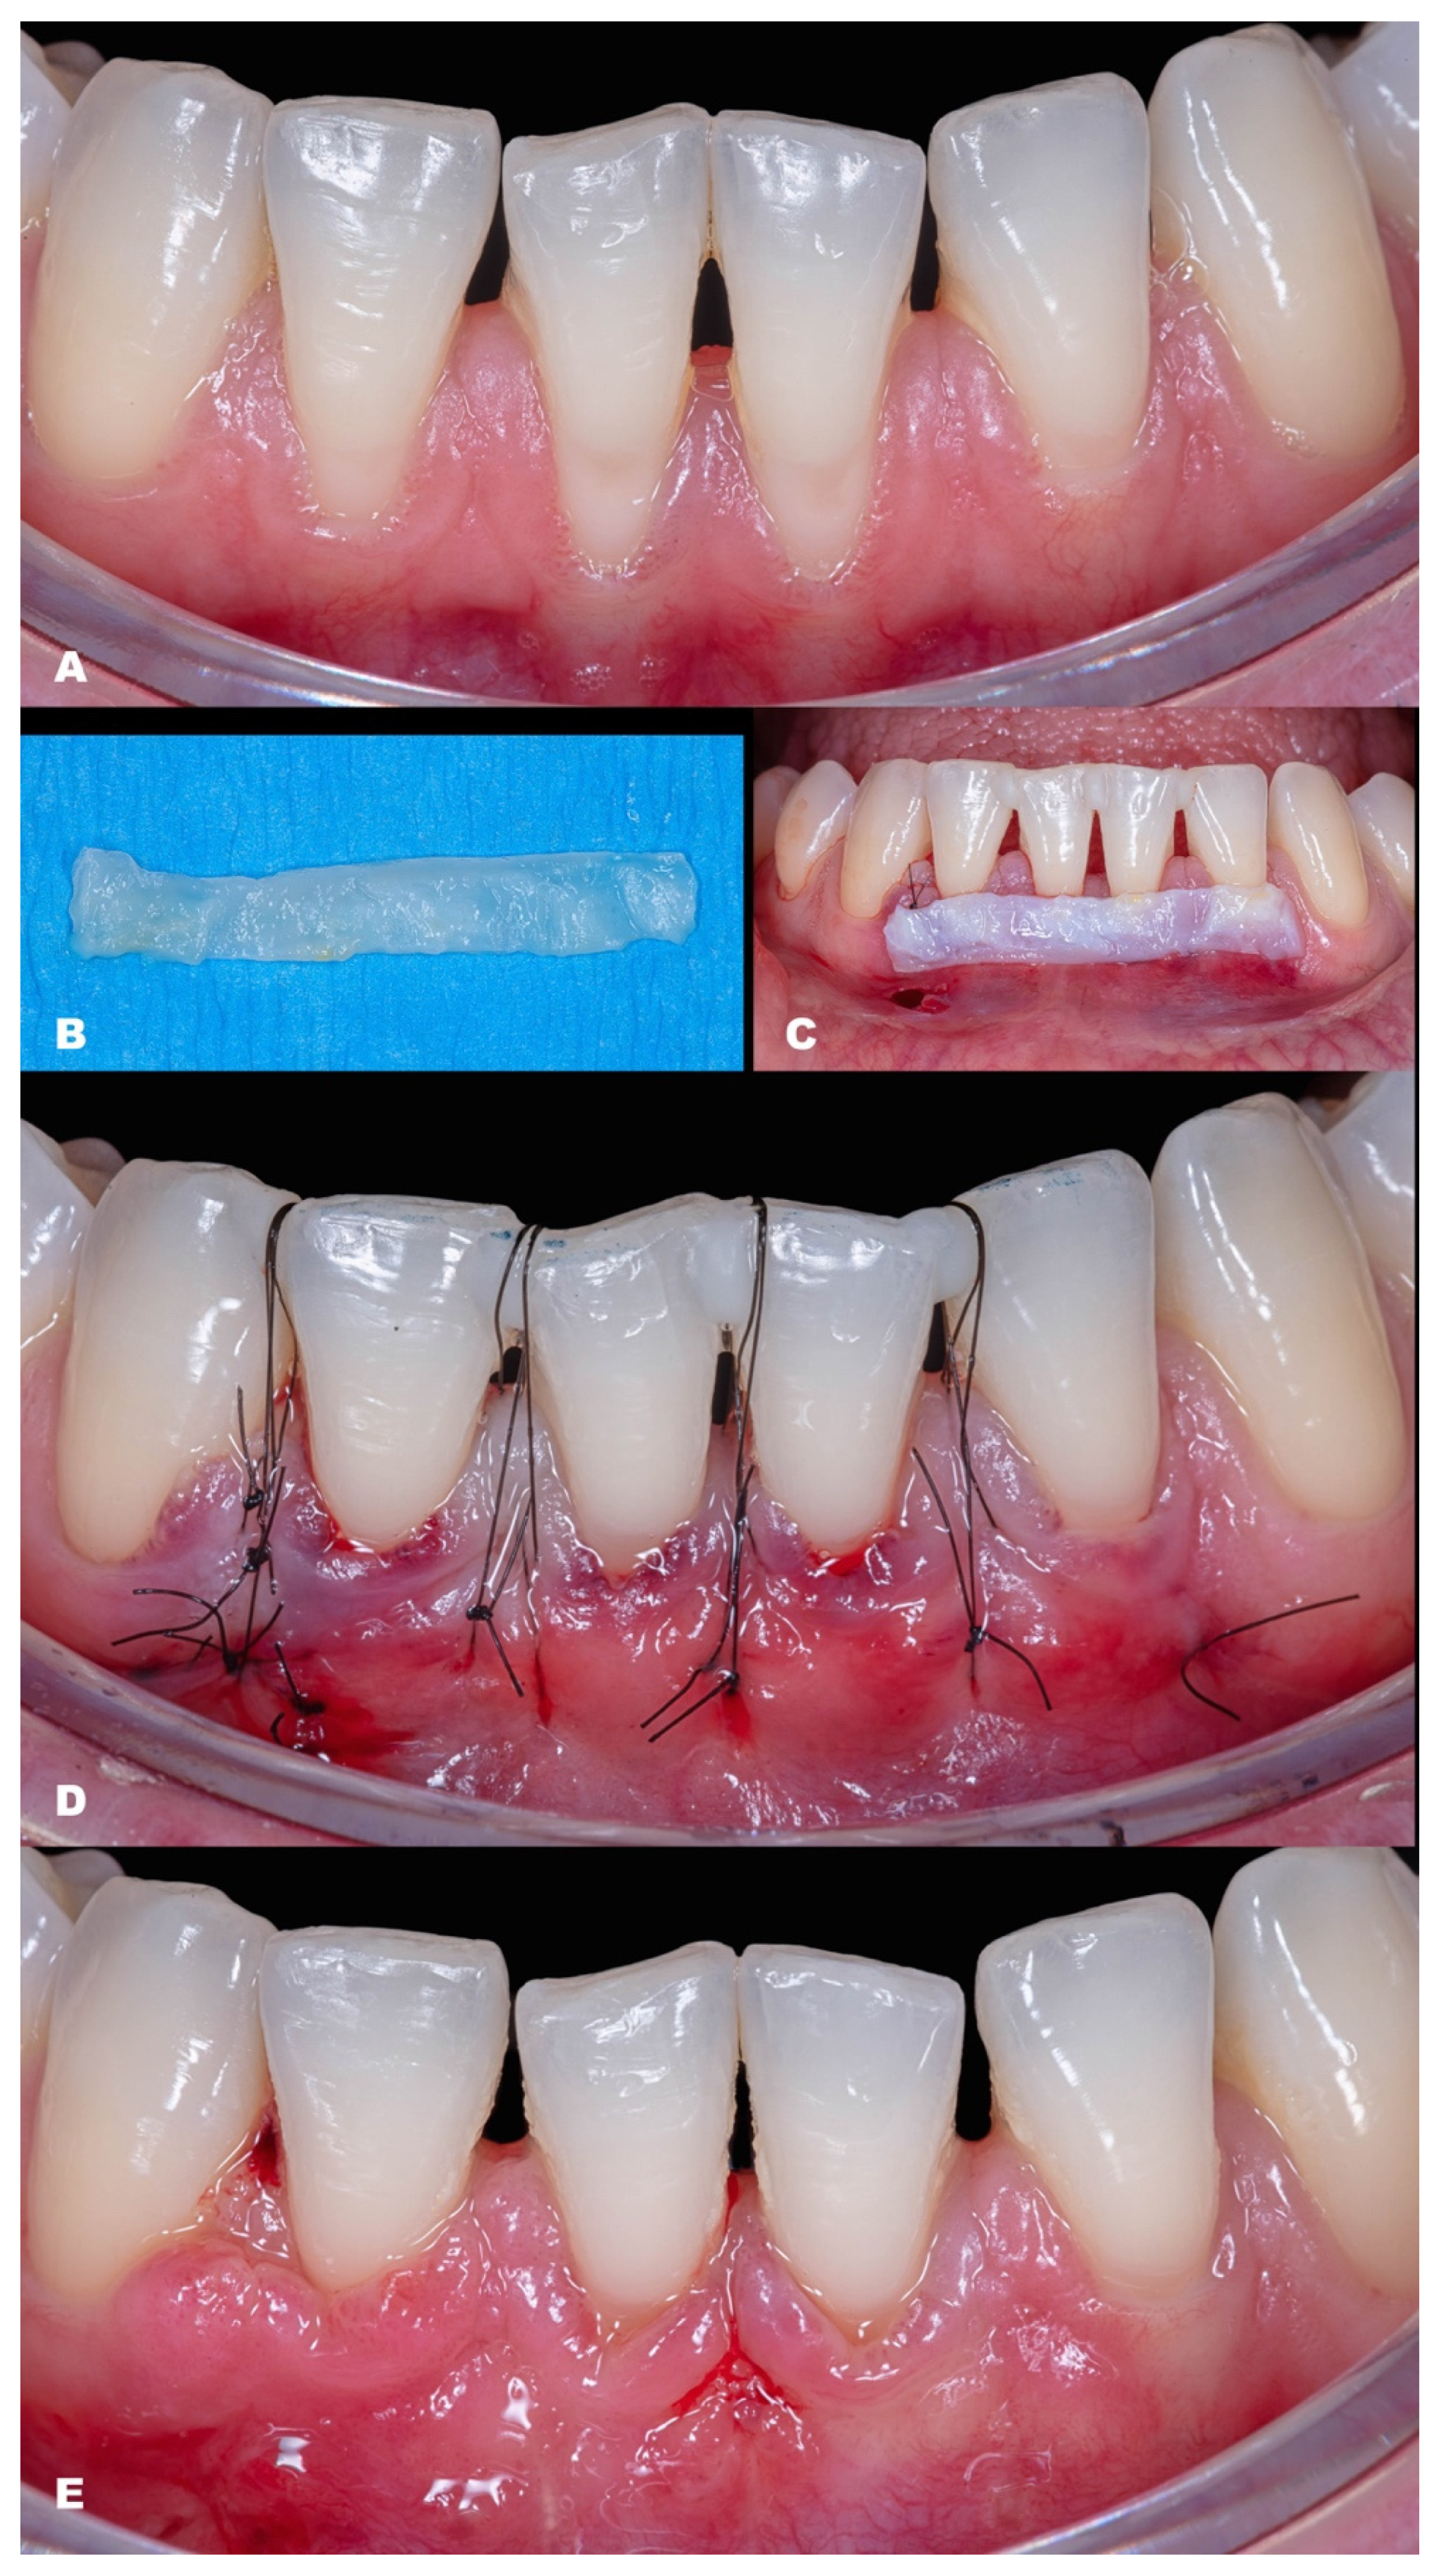

- After CTG is harvested (either subepithelial or de-epithelialized), it will be inserted in the desired site through the linear incision or intrasulcularly (Figure 1K,L).

- (7)

- The CTG will be adjusted to cover the recession (Figure 1l) and must be coronally advanced at least 1 mm coronal to the CEJ.

- (8)

- Then, MiTT should be sutured according to the personally preferred technique. It is suggested that the suture techniques slightly pull the tunnel coronal (anchored with composite or double-crossed suture [18]). The vertical incision must be sutured with one or two single sutures. It is suggested to stabilize the soft tissues using interrupted sutures, and it may be used as adjunctive material, such as a biological glue. It is suggested that the suture be removed between 7 and 14 days.

| Classification | Gender | Tooth/Teeth with REC | Initial REC Height (mm) | Initial REC Width (mm) | Initial PD (mm) | Initial KTW (mm) | Final REC Height (mm) | Final PD (mm) | Final KTW (mm) | % RC | p-Value | |

|---|---|---|---|---|---|---|---|---|---|---|---|---|

| Baseline | 6-Month Follow-up | |||||||||||

| Case 6 | RT1 | F | 43 44 45 | 1.2 2.1 1.4 | 2.6 3.1 2.8 | 2.0 1.5 1.0 | 3.0 3.8 3.8 | none | 1.5 1.0 1.0 | 2.1 2.8 5.3 | 100 100 100 | |

| Case 7 | RT1 | F | 12 11 21 22 | 1.1 1.5 2.4 1.5 | 1.5 3.0 4.0 2.0 | 1.0 2.0 1.5 2.0 | 5.4 5.0 6.3 6.9 | none | 1.0 2.5 2.5 1.5 | 4.3 5.7 6.0 6.3 | 100 100 100 100 | |